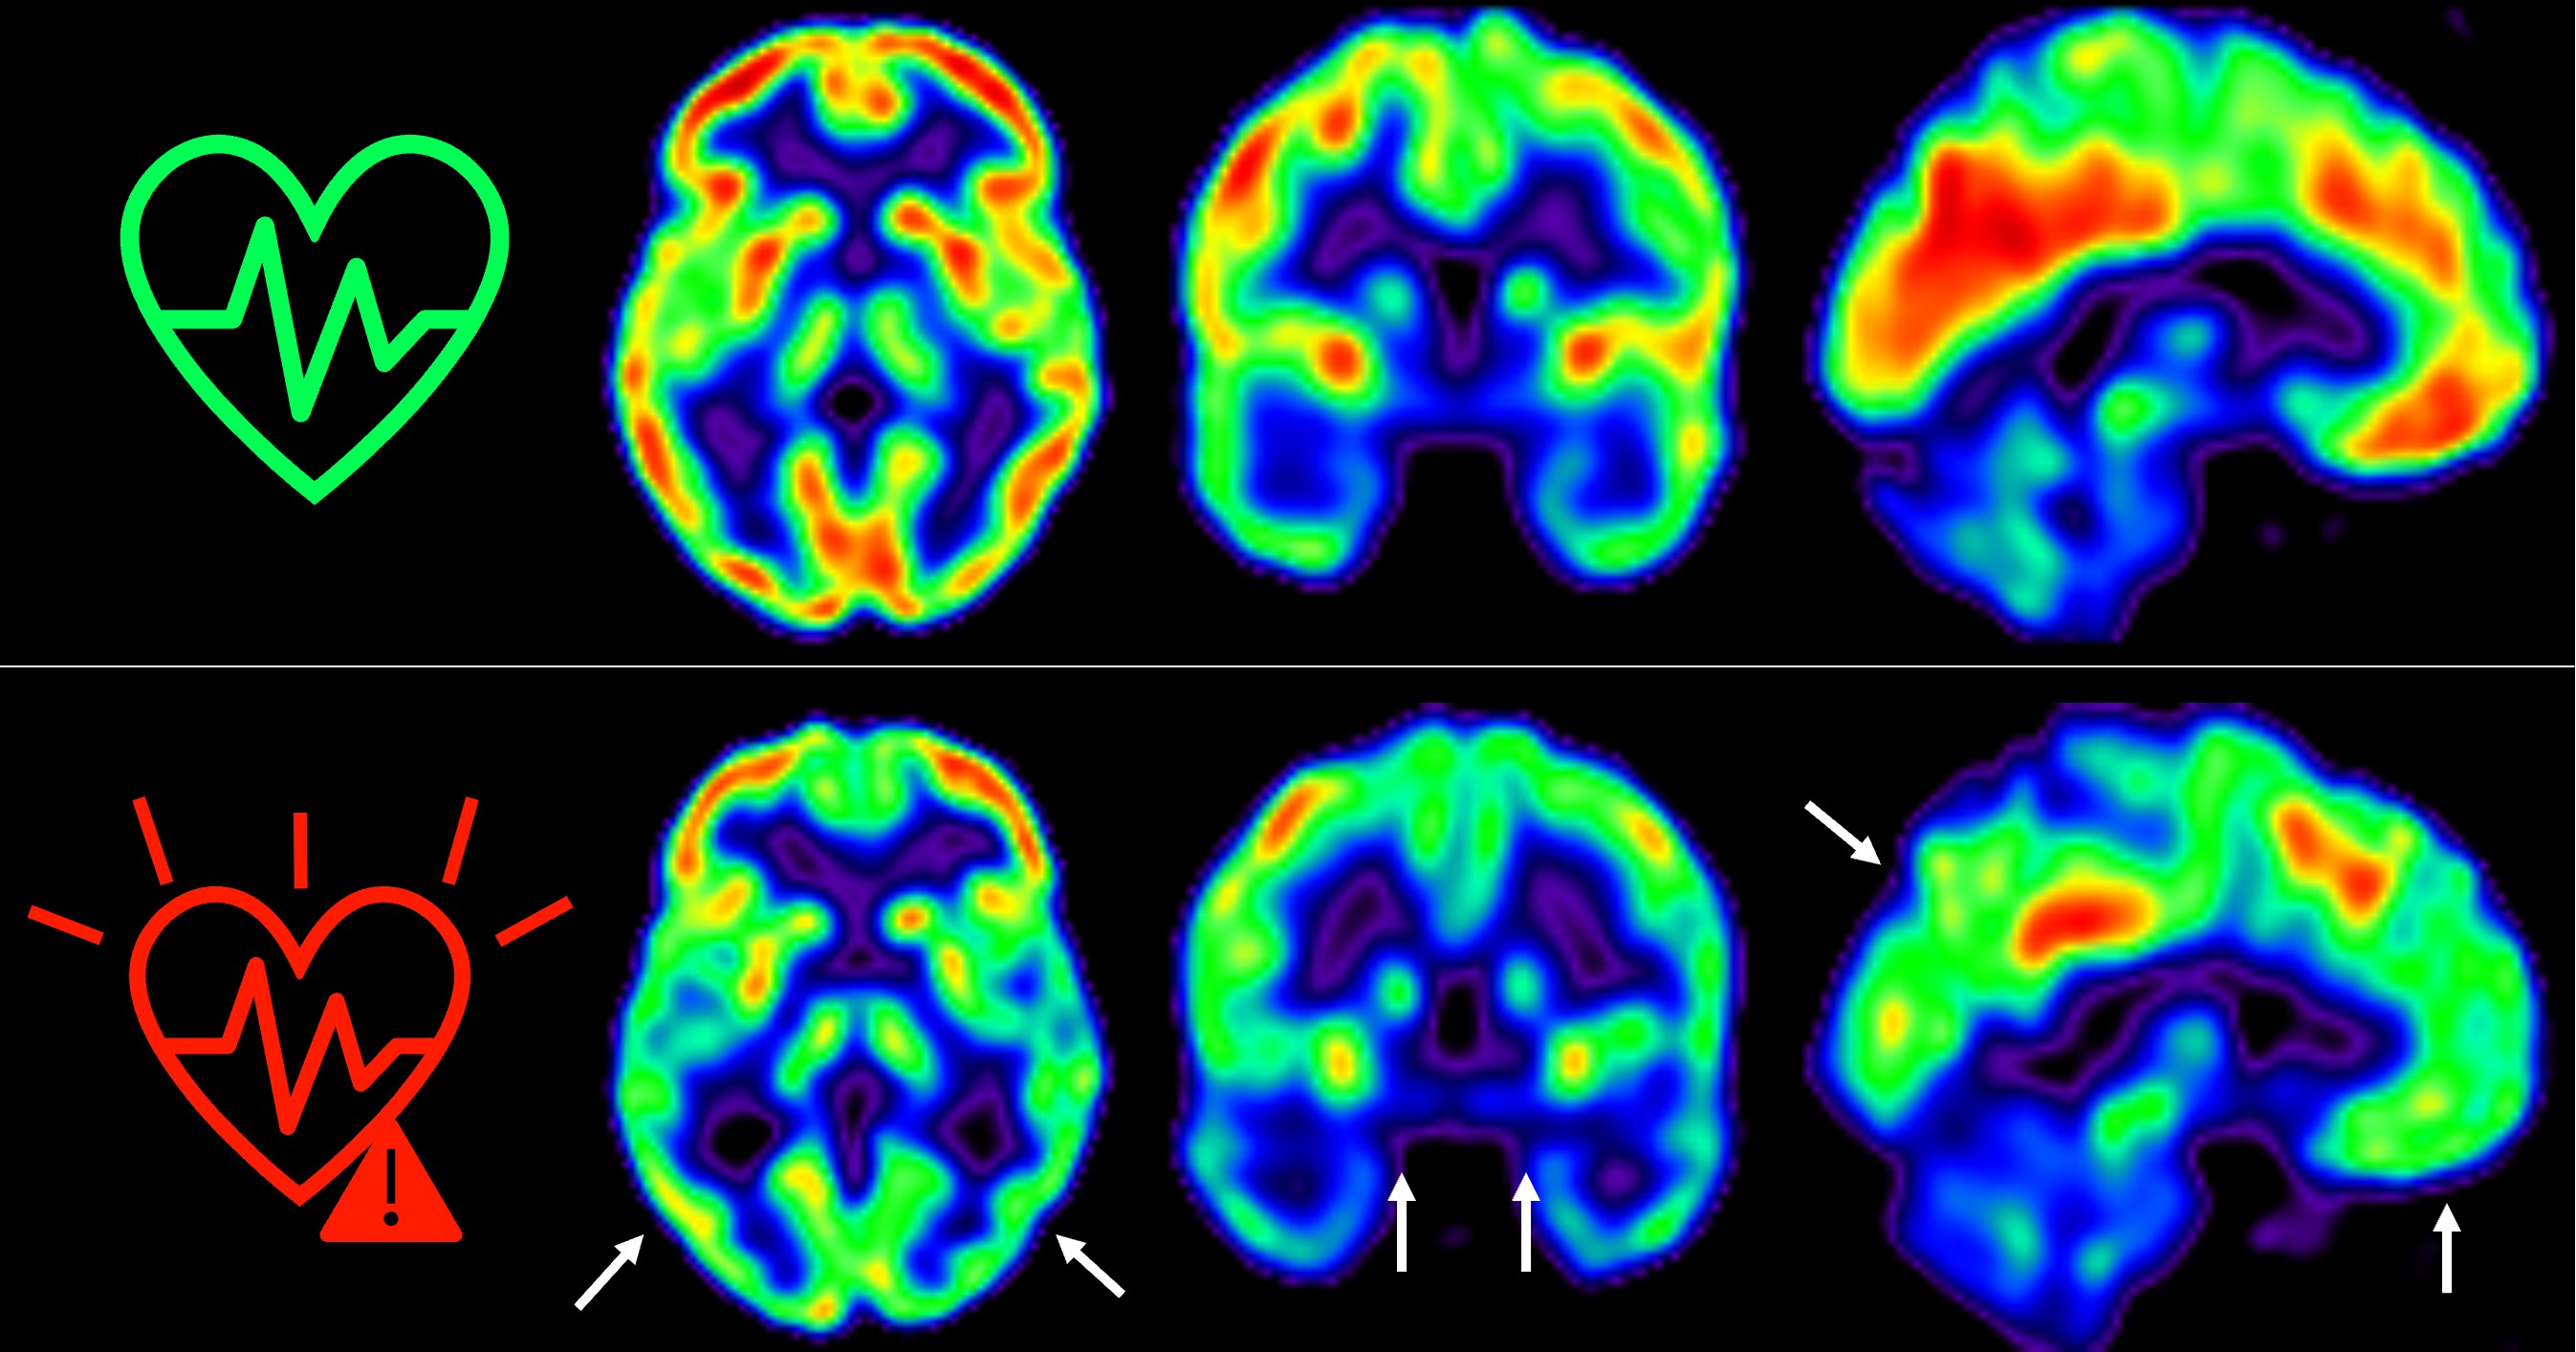

El equipo del Dr. Fuster, liderado por los doctores Marta Cortés Canteli y Juan Domingo Gispert, han seguido a estos individuos a lo largo de cinco años y han encontrado que aquellos que mantienen un riesgo cardiovascular elevado durante todo este tiempo sufren una disminución aún mayor del metabolismo cerebral medido a través de técnicas de imagen como tomografía por emisión de positrones (PET).

"Hemos detectado un declive metabólico cerebral tres veces mayor que el de personas que se mantienen en bajo riesgo cardiovascular", señala Catarina Tristão-Pereira, primera firmante del artículo y becaria INPhINIT de la Fundación "la Caixa".

Además, el equipo del CNIC descubrió que la progresión de la aterosclerosis subclínica en las carótidas durante estos cinco años se relacionaba con una disminución del metabolismo en regiones cerebrales vulnerables a la enfermedad de Alzheimer, de manera aditiva al efecto de los propios factores de riesgo cardiovascular. "Estos resultados corroboran que la detección por imagen de la aterosclerosis subclínica aporta información muy relevante", añade el Dr. Fuster, investigador principal del estudio PESA. "La relación entre el cerebro y el corazón es un tema fascinante y con este estudio hemos visto que empieza mucho antes de lo que se creía", continúa.